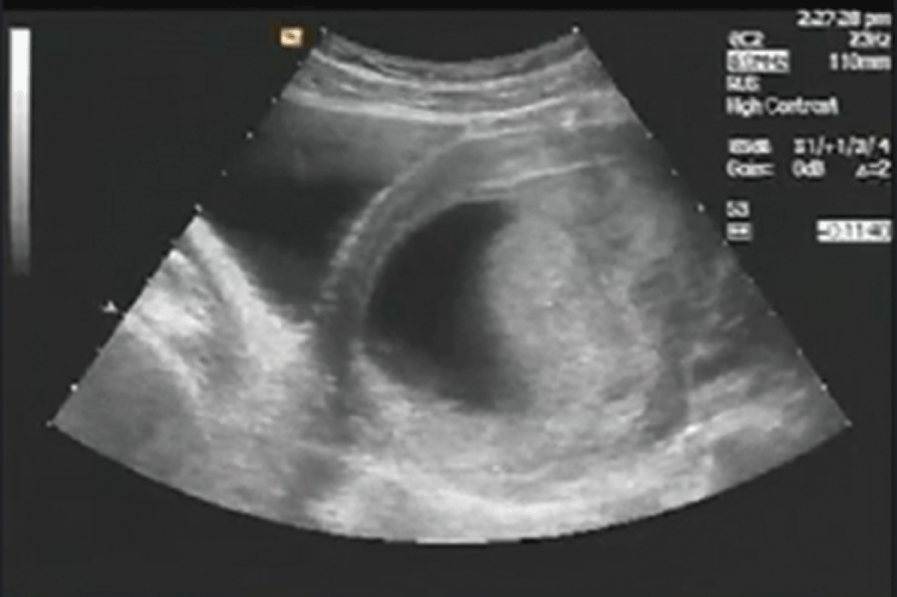

Private ultrasound dating scan (sometimes called 12 week scan or booking scan ) . We recommend that you present your dating scan results to your usual healthcare professional whose contact details we take at the time of booking . Your choice of a free rescan may be appropriate if we are unable to perform the primary purpose of this scan .

Babybond® Pregnancy Scans in Cambridge . All of our pregnancy scans are fairly priced without compromising on quality, reliability and care . If you are a mum-to-be looking for peace of mind that your pregnancy is going well, or to bond with your baby with a 4D scan , we can help you . Early pregnancy scans .

All the samples were obtained from the Pregnancy Outcome Prediction-a prospective cohort study of nulliparous women attending the Rosie Hospital, Cambridge (UK) for their dating ultrasound scan between January 14, 2008, and July 31, 2012 .